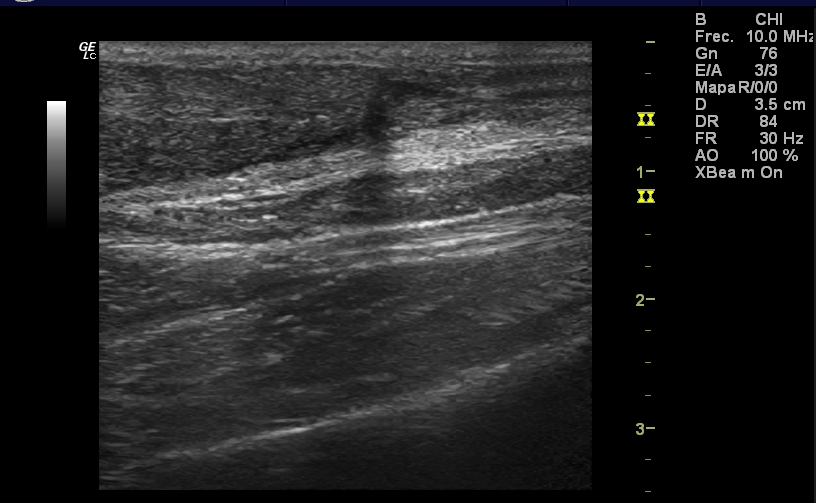

Hombre de 82 años alérgico a betalactámicos, dislipémico, hipertenso y EPOC, que es valorado en Urgencias por un cuadro catarral, tras el cual se ajusta medicación domiciliaria y se pauta levofloxacino 500 mg/día durante 5 días, ante la sospecha de reagudización con criterios de infección sobreañadida.Hallazgos ecográficos

Rotura del espesor completo de ambos tendones Aquíleos, a 4 cm del borde superior del calcáneo aproximadamente, con retracción del cabo proximal y GAP entre ambos cabos de 3 cm. No se ve derrame articular, aunque sí cierto edema de tejido celular subcutáneo.Pruebas complementarias